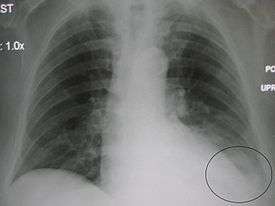

![]() Chest X-ray of a 30-year-old healthy man, with the costodiaphragmatic recess label in red ellipse | |

In anatomy, the costophrenic angles are the places where the diaphragm (-phrenic) meets the ribs (costo-).

Each costophrenic angle can normally be seen as on chest x-ray as a sharply-pointed, downward indentation (dark) between each hemi-diaphragm (white) and the adjacent chest wall (white). A small portion of each lung normally reaches into the costophrenic angle. The normal angle usually measures thirty degrees.

With pleural effusion, fluid often builds up in the costophrenic angle (due to gravity). This can push the lung upwards, resulting in "blunting" of the costophrenic angle. The posterior angle is the deepest. Obtuse angulation is sign of disease.

Chest x-ray is the first test done to confirm the presence of pleural fluid. The lateral upright chest x-ray should be examined when a pleural effusion is suspected. In an upright x-ray, 75 mL of fluid blunts the posterior costophrenic angle. Blunting of the lateral costophrenic angle usually requires about 175 mL but may take as much as 500 mL. Larger pleural effusions opacify portions of the hemithorax and may cause mediastinal shift; effusions > 4 L may cause complete opacification of the hemithorax and mediastinal shift to the contralateral side.